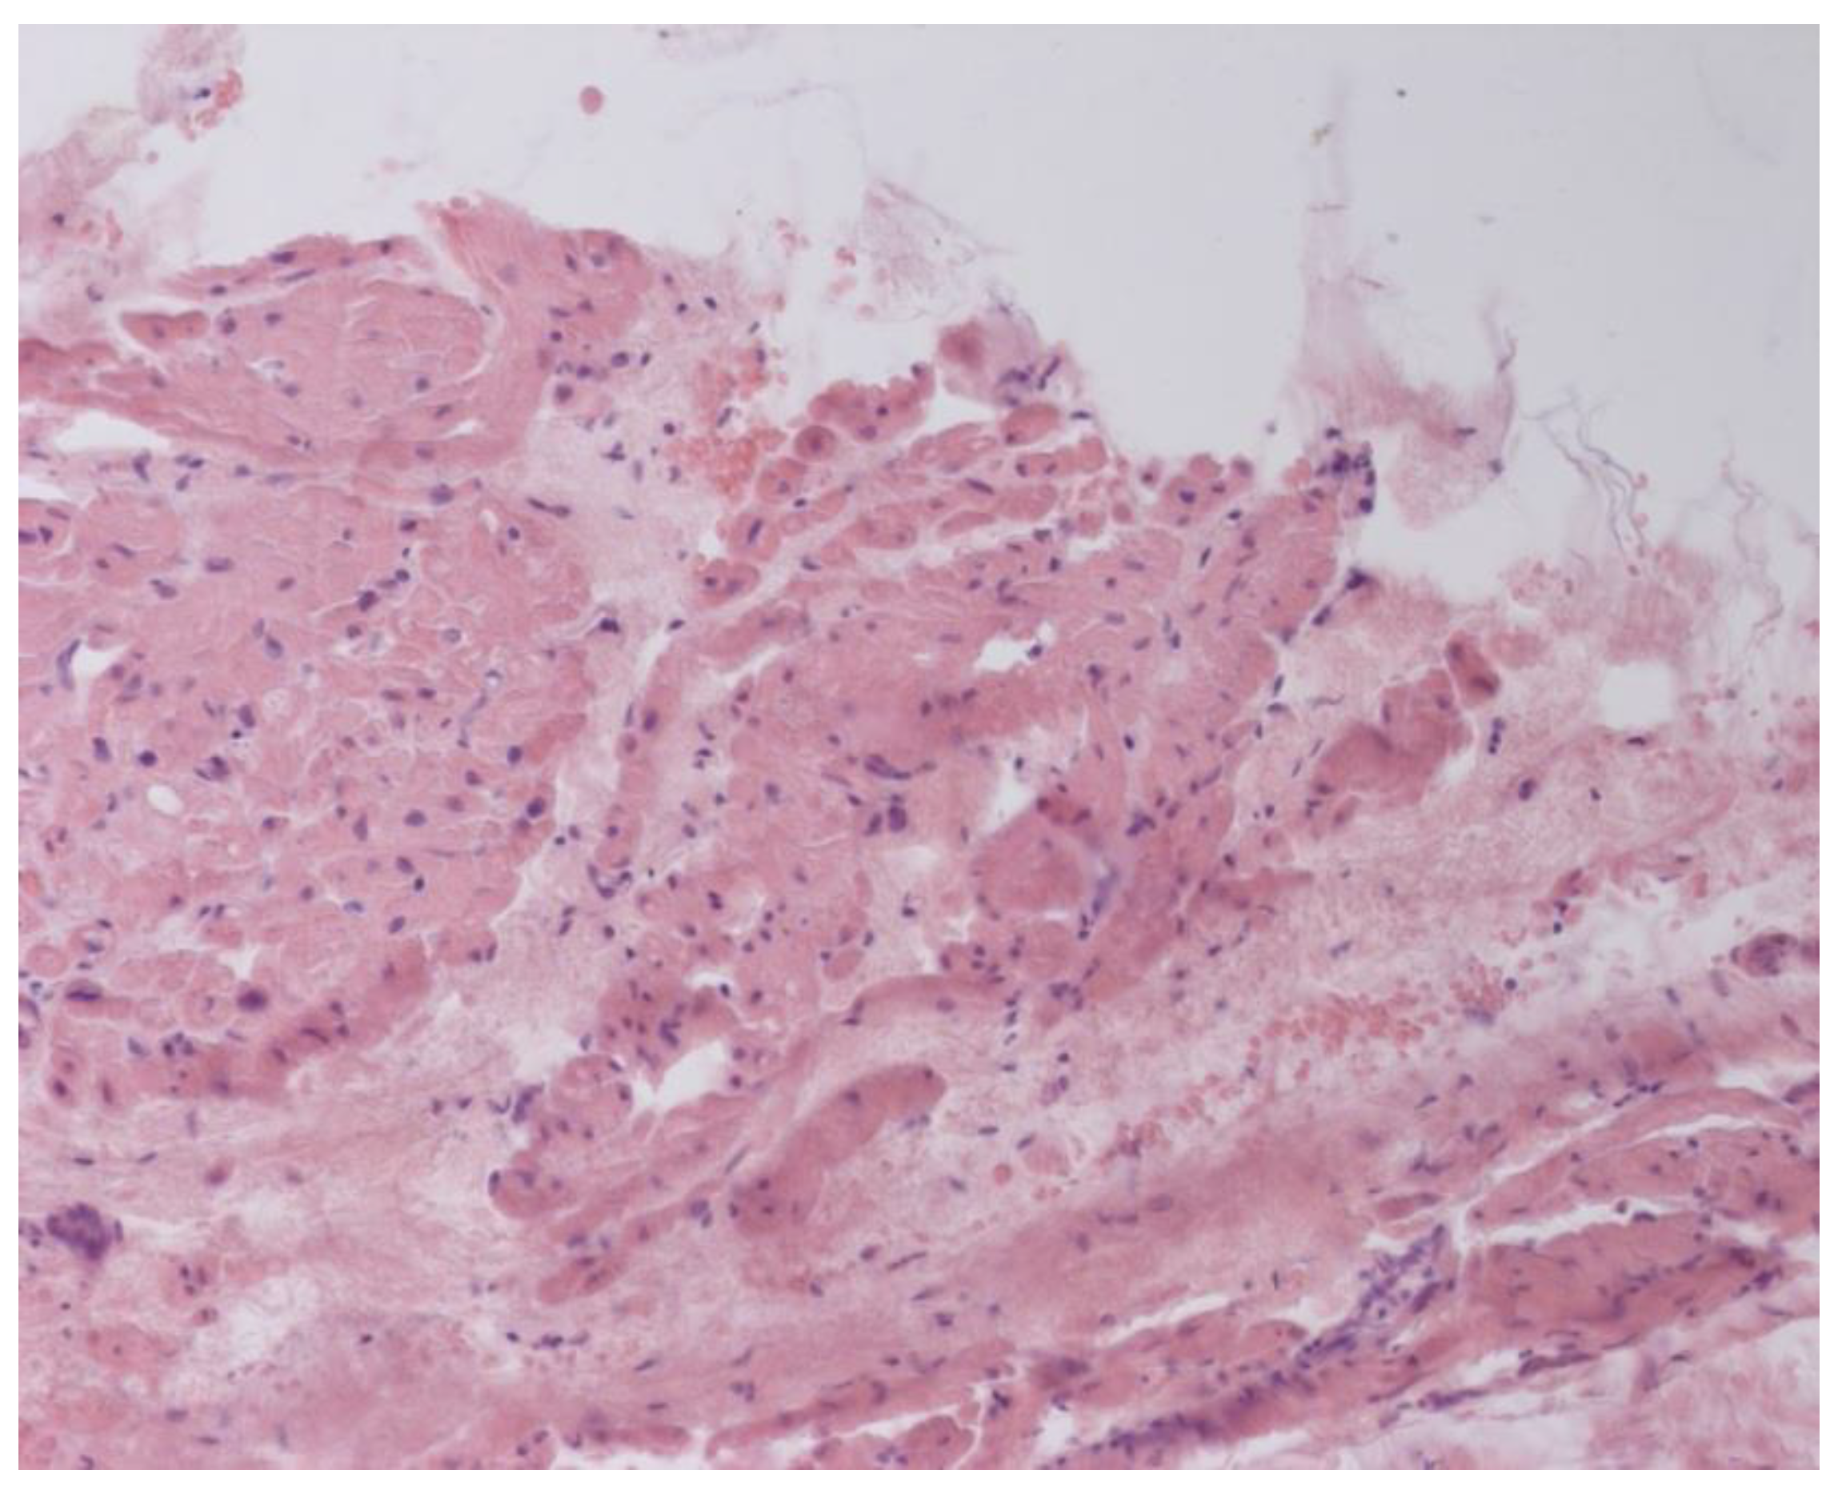

Inflammatory changes in the myocardium were detected in 32 patients (47.8%), including nine patients (28.1%) with lymphocytic infiltration of less than 14 lymphocytes per mm2 (Figure 4 and Figure 5). The data obtained with EMB from RV and IAS were comparable. Inflammatory changes in RV correspond to a similar finding in IAS, while fibrotic changes in RV correspond to the same evidence in IAS. According to the results of immunohistochemical analysis, the virus expression was detected in one of these patients (3.1%). A combination of human herpes simplex virus type 2 and Epstein-Barr was found. No virus expression was detected in the remaining patients.

According to the Dallas criteria, the presence of histological myocarditis was revealed in 23 patients (34.3%) (Figure 6). Moreover, the virus expression was detected in 18 of these patients (78.3%), according to the results of immunohistochemical analysis. One patient (5.6%) was found to express three viruses: enterovirus, human herpes simplex virus type 1, and Epstein-Barr virus; six patients (33.3%) had the presence of two viruses: one patient had a combination of parvovirus and herpes simplex virus type 2; three patients had a combination of enterovirus and herpes simplex virus type 1; and two patients had a combination of Epstein-Barr virus and human herpes simplex virus type 2. The presence of one viral antigen was detected in 11 cases (61.1%), including five patients (27.8%) with Epstein-Barr virus, three patients (16.7%) with enterovirus (Figure 7), two patients (11.1%) with human herpes simplex virus, and one patient (5.6%) with parvovirus. Another five patients (21.7%) did not have viral infection.

Figure 6. Active lymphocytic histological myocarditis, ×100. Hematoxylin-Eosin staining.